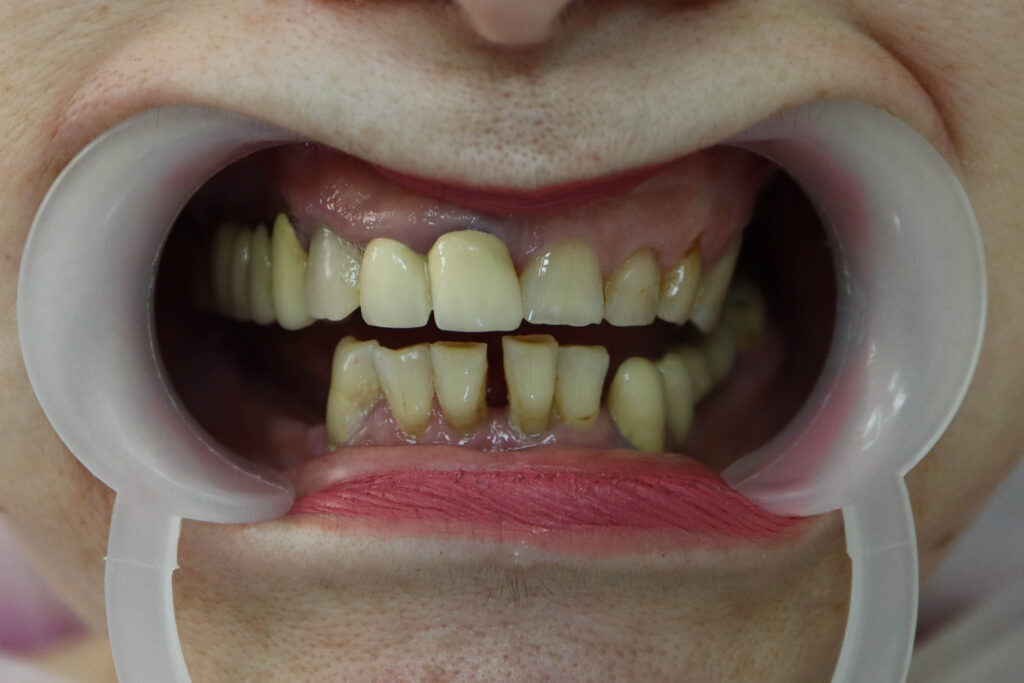

Ситуация до лечения

Диагноз: Полная адентия нижней и верхней челюстей.

пациент до имплантации